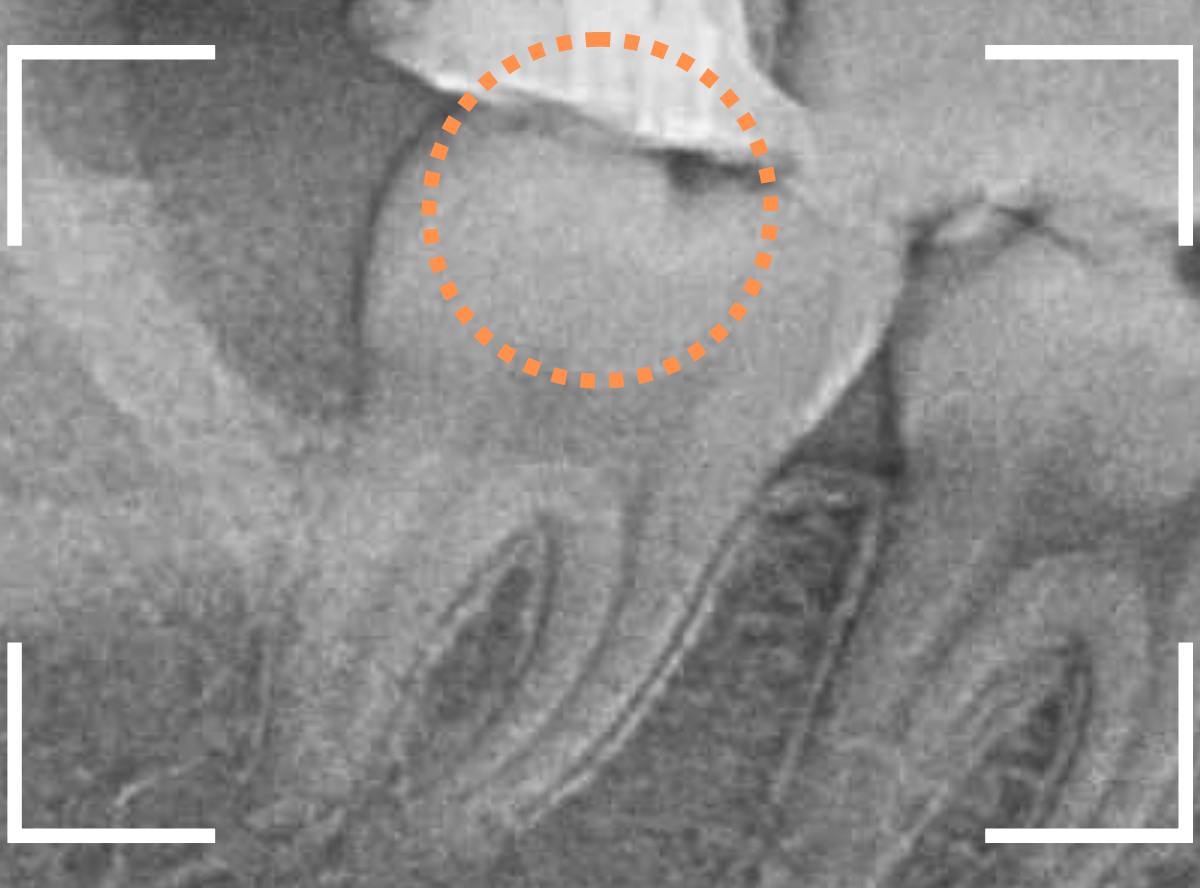

Case.15 レジンの下の深い虫歯

奥歯で咬んだ時に、痛みを感じるという訴えで来院された患者さんです。

パッと見は特に問題なさそうな状態ですが、大きなレジン治療がしてあり、レジンの奥もボヤっと黒っぽく見えてアヤシイ感じです。

レントゲン写真で確認します。

青い線が神経、赤い線が虫歯です。

神経に触ってしまいそうなほどの大きな虫歯です。

(隣の歯も虫歯がありそうです)